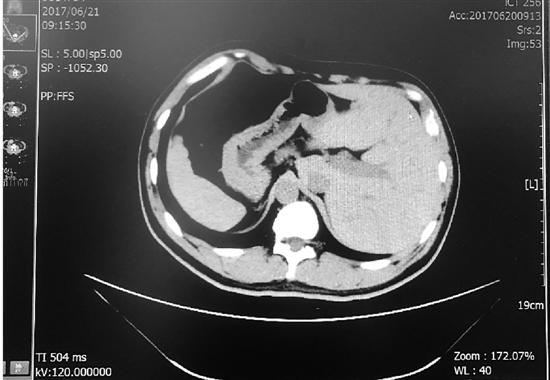

圖為影像片

張先生今年41歲,家住溫州市區,已經反復便血約十年,近兩三個月出血突然增多。今年6月中旬,他來到溫州醫科大學附屬第二醫院(以下簡稱附二醫)做檢查。這一查,竟然查出了直腸癌,腫瘤的直徑有5厘米左右,幸運的是還沒有發生病灶轉移,需要立即切除。

得知需要手術,張先生脫口而出的第一句話就是:“我是個鏡面人。”這意味著,他的心、肝、脾等臟器都在與常人相反的位置,腸道也是如此。“一般人的大腸是順時針的,闌尾在右側,而鏡面人的大腸是逆時針方向,闌尾在左側。”